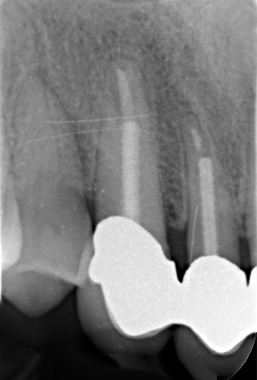

Langzeitkontrolle

Langzeitkontrolle (definitiver Zahnersatz im April 1997) knapp vier Jahre nach Wurzelfüllung im Juni 2000 mit röntgenologischer vollständiger Ausheilung

Langzeitkontrolle im Oktober 2003 also sechs Jahre und neun Monate nach Wurzelfüllung mit röntgenologisch unauffälligem Parodontalspalt physiologischer Breite. Eine Wurzelspitzenresektion hätte den Zahn unnötigerweise geschwächt und wäre mit einer fraglichen Prognose verbunden gewesen